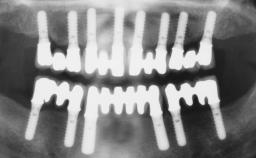

Immediate Loading of Four Implants in the Mandible and Final Restoration with a Full-Arch Metal Framework FDP

A fully edentulous 65-year-old woman was referred to our clinic for esthetic and functional dental rehabilitation. The patient presented with inadequate complete maxillary and mandibular prostheses, insufficient vertical dimension, and extensive tooth wear. The clinical examination and anamnesis showed no local or systemic contraindications, no signs or symptoms of bruxism, and an absence of smoking habits. The treatment proposed was implant placement in the mandibular interforaminal area and immediate loading with a fixed definitive prosthesis. A removable mucosa-supported complete prosthesis was indicated for the upper jaw, since its bone structure offered satisfactory retention and the financial condition of the patient disfavored a full-mouth implant-supported rehabilitation.

# of Implants 4

Type of Implants One-Piece

Defining Characteristics Fully edentulous lower jaw to be rehabilitated with two or more implants

Modality 3 or 4 interforaminal implants

Defining Characteristics Fully edentulous lower jaw to be rehabilitated with an implant-borne fixed dental prosthesis

Loading Protocol Immediate

Retention Screw-retained, with 4 or more splinted implants Screw-retained, with 4 or more splinted implants